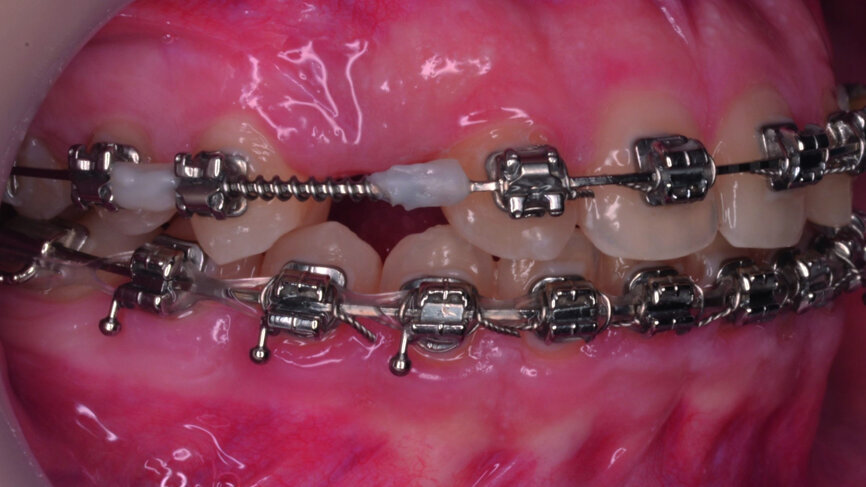

- Implants space opening: substitute laterals with canines (Figs. 23–25) and substitute canines with first premolars (Figs. 26–28).

- Verifying the implant site width (Fig. 32) and provisory implants and crowns placement (Fig. 33).